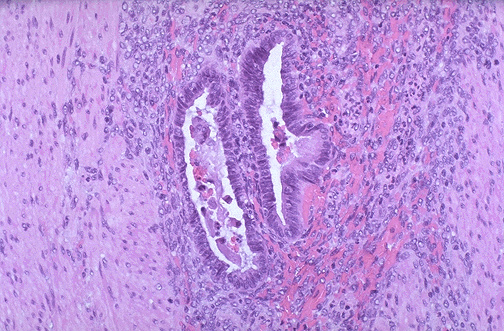

Image 3.3

Microscopically, the lesions on the serosal surfaces are composed of both endometrial glands and stroma with hemorrhage.